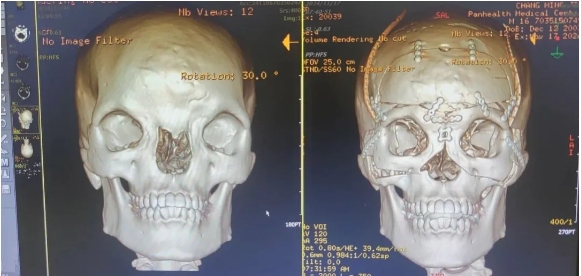

根據(jù)調(diào)查,正常男性的正??艟嗥骄鶠?8mm,而初晨的雙眼內(nèi)眥角間距71mm,影像診斷報(bào)告顯示骨性眶間距55.69mm,兩側(cè)鼻骨低平、發(fā)育不良,已屬于最嚴(yán)重的Ⅲ度。

術(shù)前,整形外科劉斌團(tuán)隊(duì)聯(lián)合醫(yī)院影像中心,為初晨完善顱頜面部CT三維重建,進(jìn)行全面評估。為精準(zhǔn)的測量截骨量以防止術(shù)后復(fù)發(fā)和矯正不足,劉斌團(tuán)隊(duì)選擇利用計(jì)算機(jī)輔助技術(shù)模擬多次切割,來設(shè)計(jì)精準(zhǔn)的截骨線,從而避免可能出現(xiàn)的遠(yuǎn)期并發(fā)癥,并達(dá)到確切的美學(xué)效果。

手術(shù)非常順利,術(shù)后CT影像診斷報(bào)告顯示(如下圖),手術(shù)效果非常好,初晨兩眼骨性距離縮短至27mm,已在正常男性眼距范圍內(nèi)。